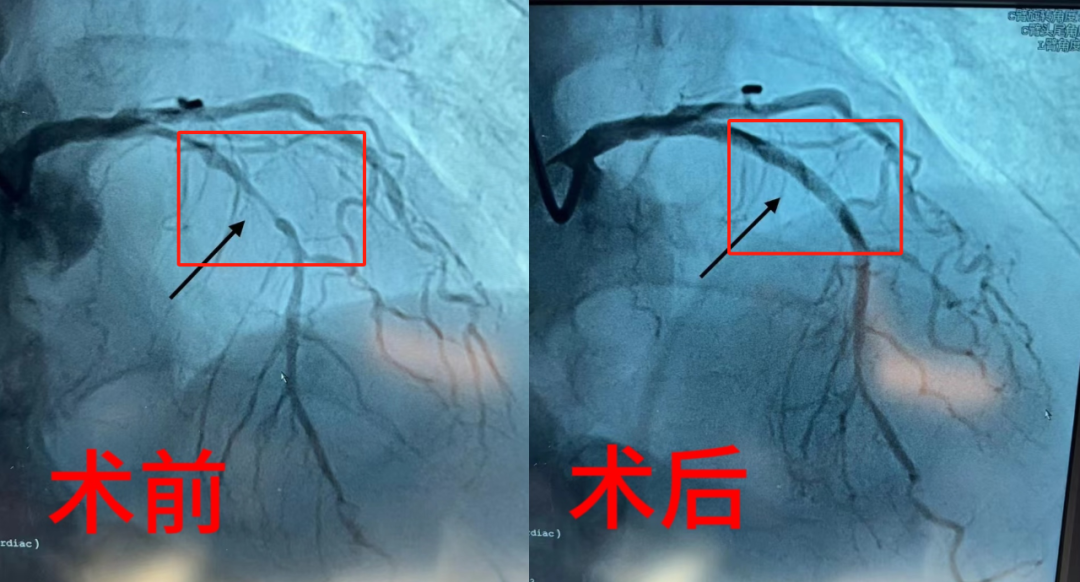

带状疱疹疼痛或掩盖心绞痛风险,患者应提高警惕

2024-05-07详情